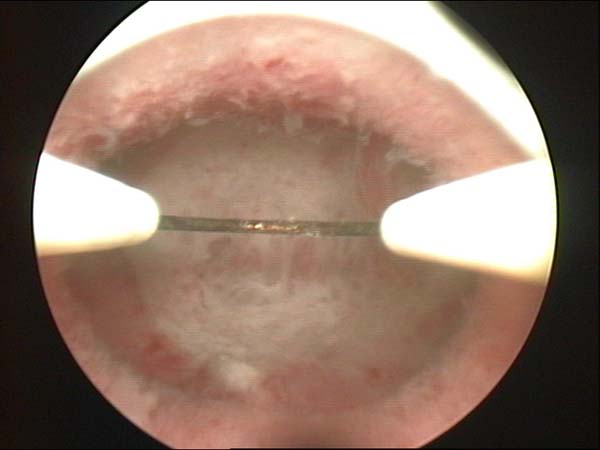

- Résection hystéroscopique d'un septum utérin pour fausses couches à répétition

- Photos de l’hystéroscopie

Photos de l’hystéroscopie | Dr N Layyous